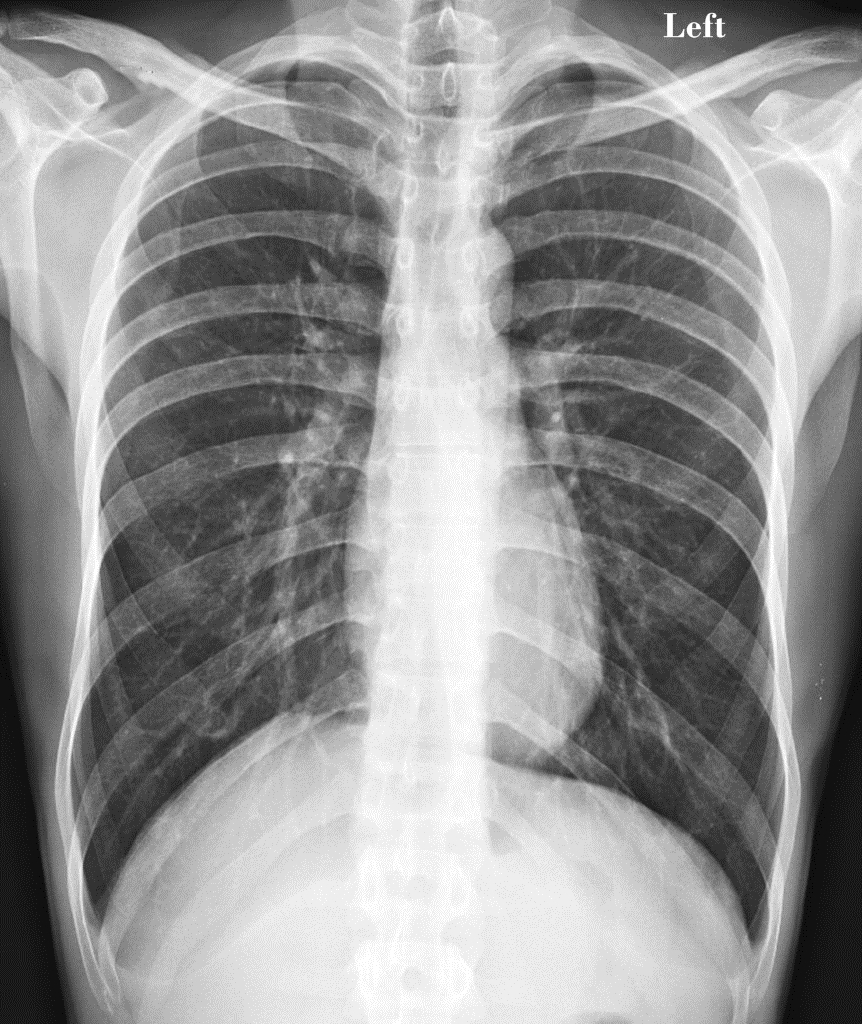

When Katherine first started to feel sick, she thought she had the flu or some other type of respiratory infection. She had a cough, trouble breathing, and chest pains. This is part of what makes mesothelioma so insidious. This is a cancer that attacks the lining of tissue around the lungs. It is most often caused by exposure to asbestos, but it does not develop into symptoms until decades after the exposure occurs.

In the meantime, people like Katherine have no idea that they are getting sick. When they do start to experience symptoms, they are often diagnosed as having an infection, pneumonia, or even lung cancer. Luckily for Katherine, although she was not diagnosed correctly right away, she still received her diagnosis when the cancer was in an early stage. Others are not so lucky and do not get an accurate diagnosis until much later.

Katherine opted for the most aggressive and riskiest treatment option, but also the one most likely to cure her cancer. As optimistic as ever, Katherine underwent an extrapleural pneumonectomy. Her surgeon removed the tissue called the pleura, in which the cancer originated, her entire right lung, and part of her diaphragm. She followed up this major and risky surgery with months of radiation treatment to try to kill every last cancer cell.